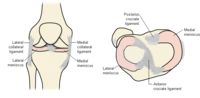

Anatomical structures around the menisci

Created by BMJ Publishing Group